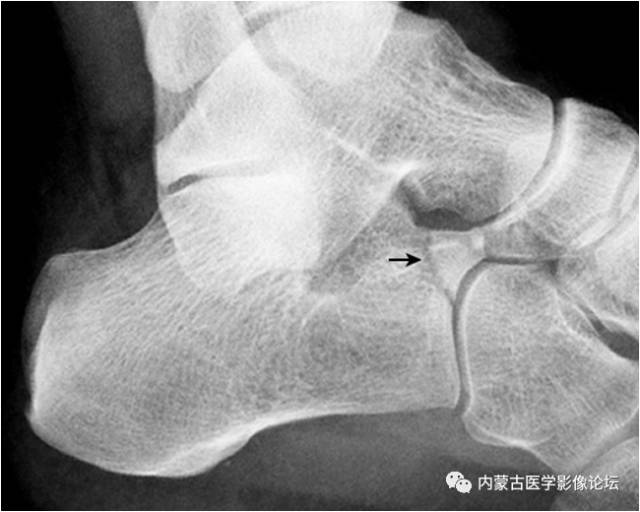

7.跟骨副骨:位于距骨、跟骨、舟骨及骰骨所围成的间隙内,呈小的骨性突起(箭头),为正常变异。需与跟骨前缘的撕脱骨折鉴别。CT 矢状面重建图像清晰显示该副骨与各骨的关系。